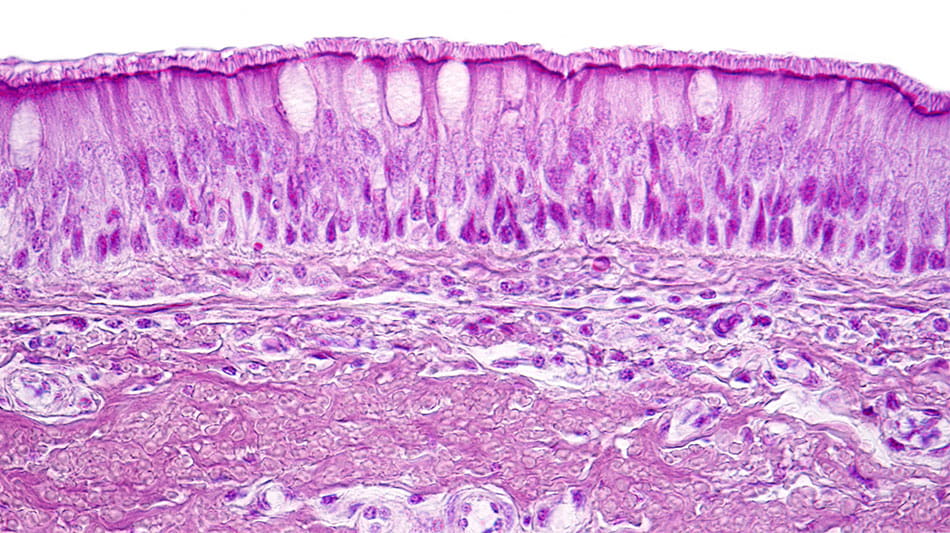

Far from being a simple barrier, the epithelium is an active immune organ. It lines the respiratory tract, defending against allergens, pollutants, bacteria and viruses.12

Light micrograph showing the respiratory epithelium. This protective tissue lines the respiratory tract, acting as both barrier and immune sentinel against pathogens and irritants.12

In people with CRSwNP, this protective barrier can become compromised and mounting evidence points to impairment of the epithelial barrier as playing an important role in disease pathophysiology.13-16 When that happens, the epithelium releases “alarmin” cytokines such as thymic stromal lymphopoietin (TSLP), IL-33 and IL-25, which set off a chain reaction of inflammation that can fuel polyp formation and chronic symptoms.13-16